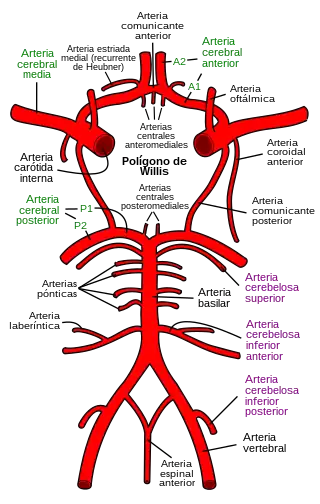

- Tipo I: consiste en únicamente estrechamiento en la mitad anterior del polígono de Willis (Bifurcación de la carótida, ACM proximal, y ACA).

- Tipo II: también incluye la arteria comunicante posterior (ACoP).

- Tipo III: afecta también las arterias cerebrales posteriores (ACP). Como resultante, las arterias lentículoestriadas están extremadamente dilatadas para brindar flujo colateral; pueden verse en la angiografía como los vasos moyamoya que forman una red de microvasos. Pueden observarse también anastomosis transdurales y leptomeníngeas.

- Las arterias que constituyen el polígono de Willis (ACA, ACM, y ACoP) muestran estenosis o grados variables de oclusión debido a engrosamiento fibro-celular de la íntima, una ondulación de la lámina elástica interna y adelgazamiento de la capa media.

- Numerosos canales vasculares pequeños (perforantes y ramas anastomóticas colaterales) se observan alrededor del polígono de Willis.